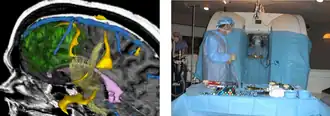

Left: 3D rendering. Right: Open MR system

Left: 3D rendering. Right: Open MR system -